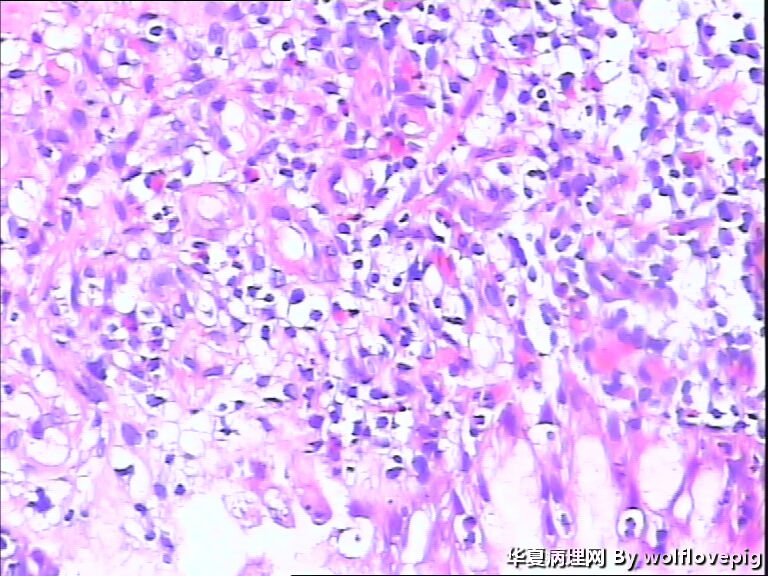

男,60y,胃窦呈结节样改变。

图2

黏液腺癌。

肿瘤中含有50%的细胞外黏液池,黏液中漂浮着散在或串珠状的癌细胞,癌细胞为富含黏液的柱状细胞及印戒细胞。